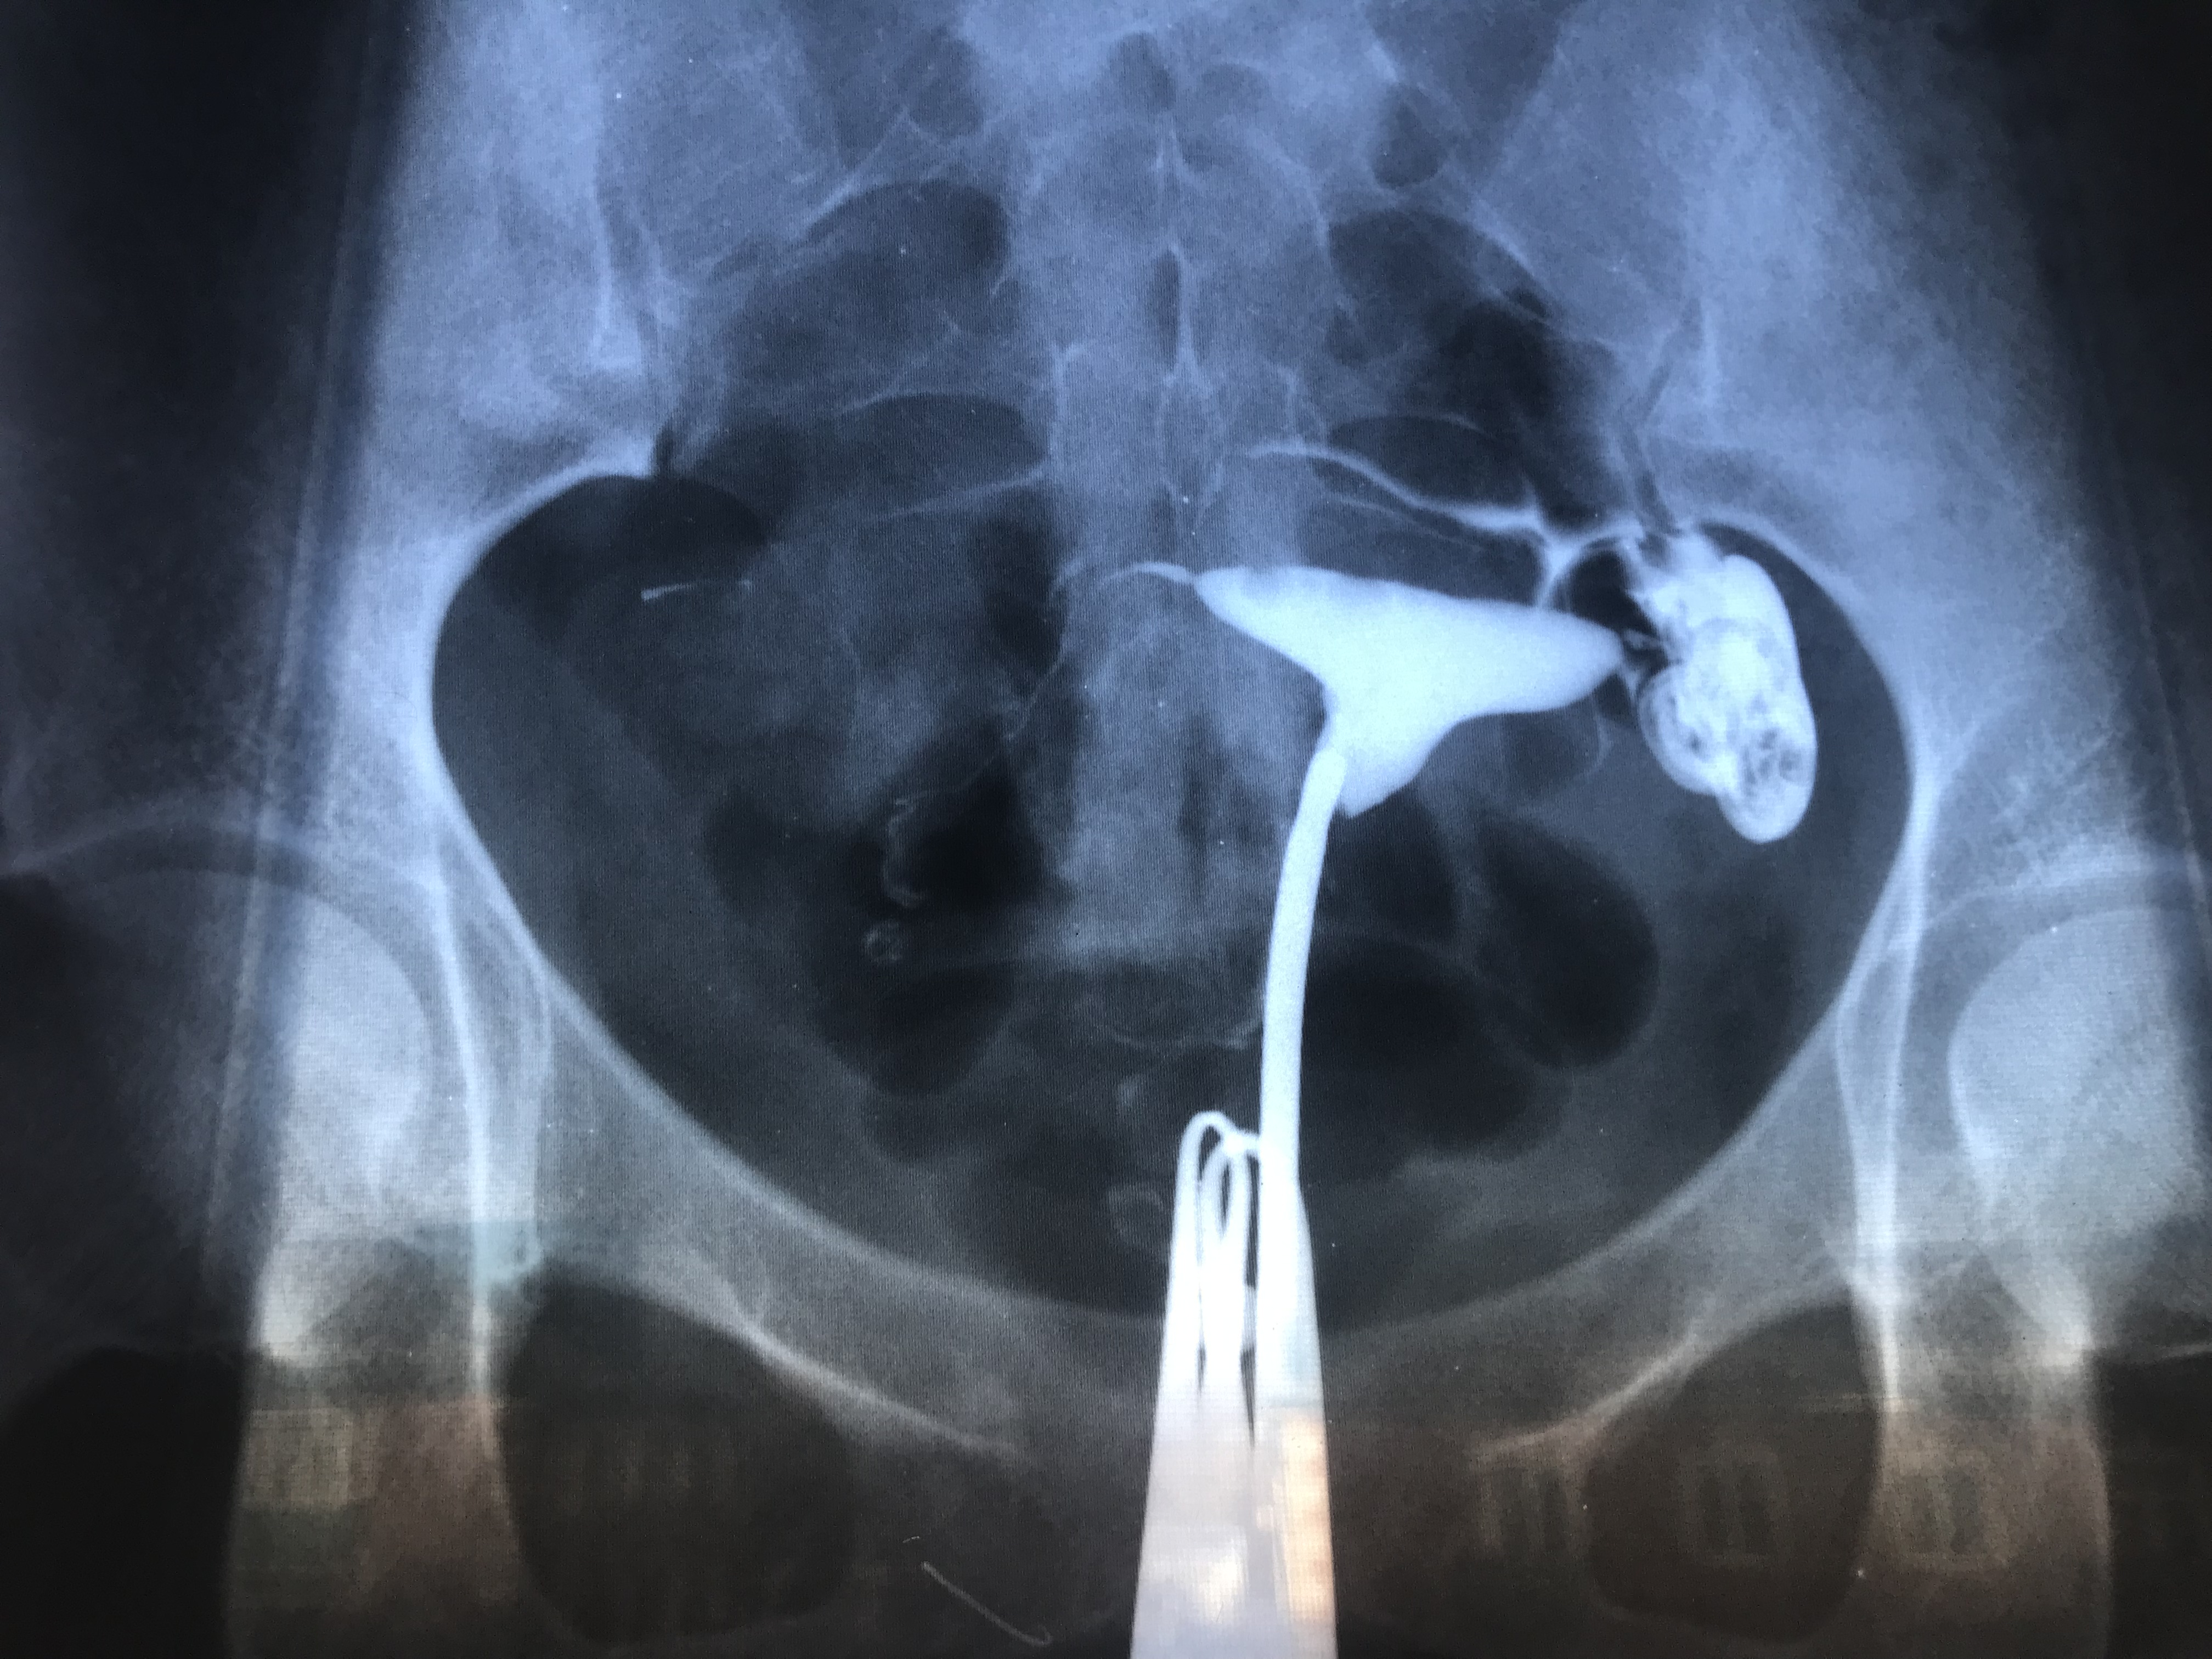

Медицинские снимки: Проходимость маточных труб

Раздел: Кадры-подсказки